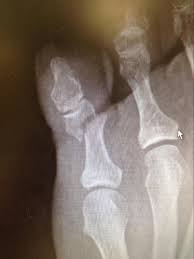

Scielo Brasil Hallux Proximal Phalanx Fracture In Adults An Overlooked Diagnosis Hallux Proximal Phalanx Fracture In Adults An Overlooked Diagnosis